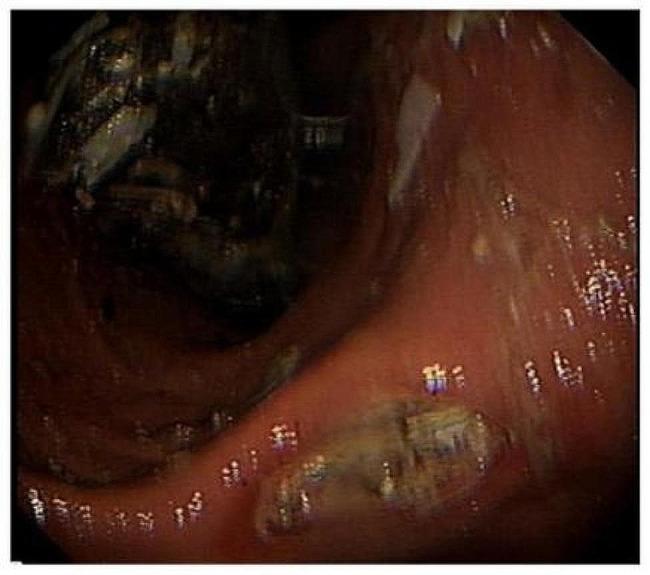

Gastric bezoars secondary to mixed infection with Sarcina ventriculi and G + bacilli: a case report.

Sarcina ventriculi is a bacterium with a specific histological morphology and infection can present with symptoms such as abdominal pain, nausea, vomiting and occasionally fatal complications. Delayed gastric emptying is regarded as the most significant risk factor for infection. Its pathogenicity is currently unknown and treatment options are inconsistent. Here we report a case of gastric bezoars secondary to a mixed infection of Sarcina ventriculi and G + bacilli, which is diagnosed by a pathological biopsy.